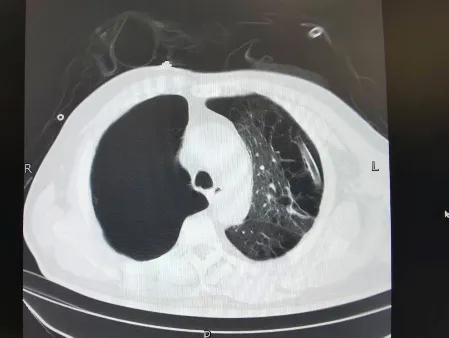

术前肺CT